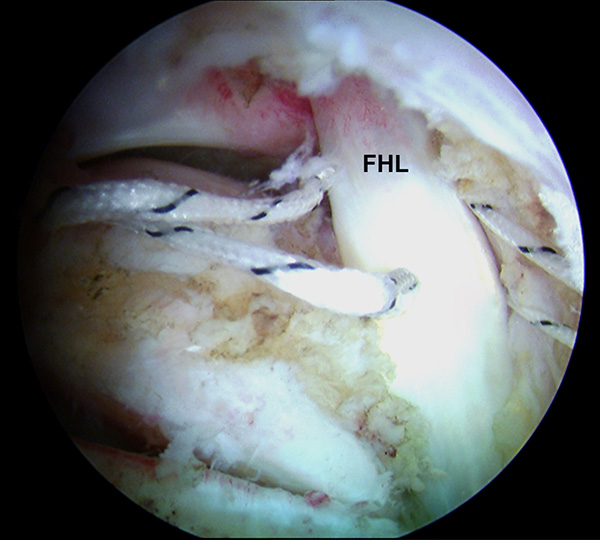

Abbildung 4, Video 1

Einführen des 4,0 mm Arthroskops über den posterolateralen Zugang und des Shavers über das posteromediale Portal. Es wird zunächst ein Weichteildebridement im Kagerschen Raum durchgeführt, bis die Flexor hallucis longus-Sehne (FHL) identifiziert werden kann (siehe auch Kapitel „Dorsale Arthroskopie des oberen und unteren Sprunggelenks“, Abbildungen 5-10).

Zum Lesen der Bildbeschreibung und zur Vollansicht bitte das Bild anklicken. Foto: M. Galla.